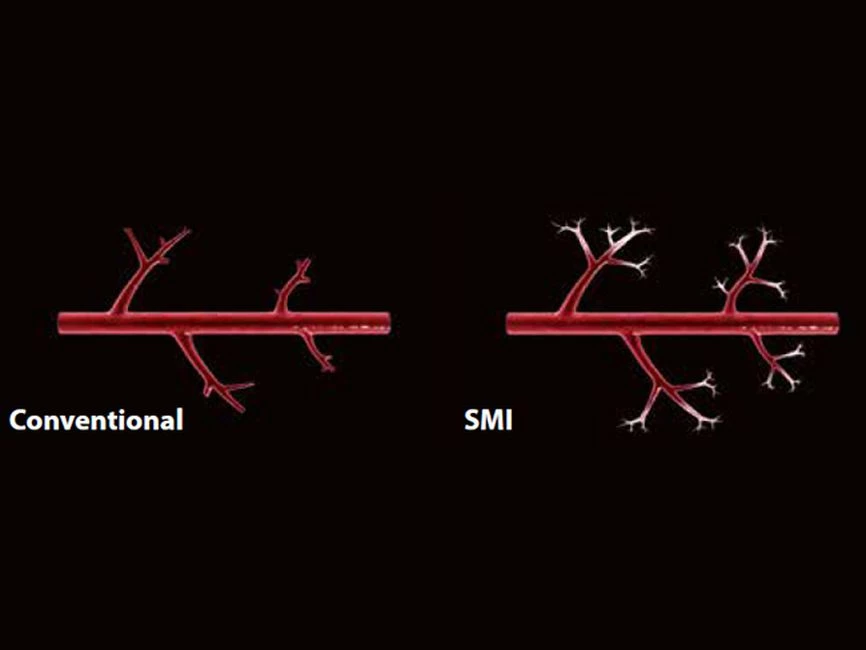

- SMI. Опция, упрощающая визуализацию микроциркуляторного русла. С ее помощью обследуются сосуды с низкой интенсивностью кровотока, изучаются наиболее тонкие структуры. SMI упрощает диагностику новообразований, минимизирует вероятность ошибки.

Уровень сосудистой визуализации SMI в сочетании с высокой частотой кадров повышает диагностическую достоверность при оценке поражений, кист и опухолей.

SMI с цветовой кодировкой позволяет одновременно отображать информацию о потоках и оттенках серого с высокой временной и пространственной информацией.